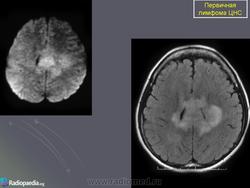

Первичные лимфомы ЦНС. Вс, 22/05/2011 - 21:45 #1 Катенёв Валенти... Не на сайте Был на сайте: 7 лет 5 месяцев назад Зарегистрирован: 22.03.2008 - 22:15 Публикации: 54876 Продолжение.Приложения:

Продолжение.